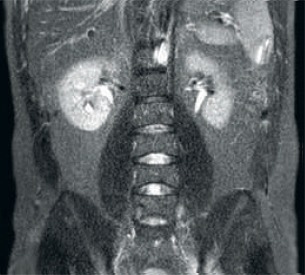

Результат: зашумленные изображения при использовании одинаковых параметров сканирования

Улучшенная согласованность и качество изображений Технология приема РЧ-сигнала dStream выполняет оцифровку МР-сигнала прямо в РЧ-катушке, что позволяет увеличить соотношение сигнал/шум на 40% (макс.)* для всех изображений. Оптимизация рабочего процесса и повышение пропускной способности Задняя катушка, встроенная в деку стола, позволяет избежать дополнительных действий с ней в 60% исследований. Легкие передние катушки, соответствующие анатомическим областям, можно перемещать самостоятельно, а однокабельное соединение делает рабочий процесс проще и быстрее.